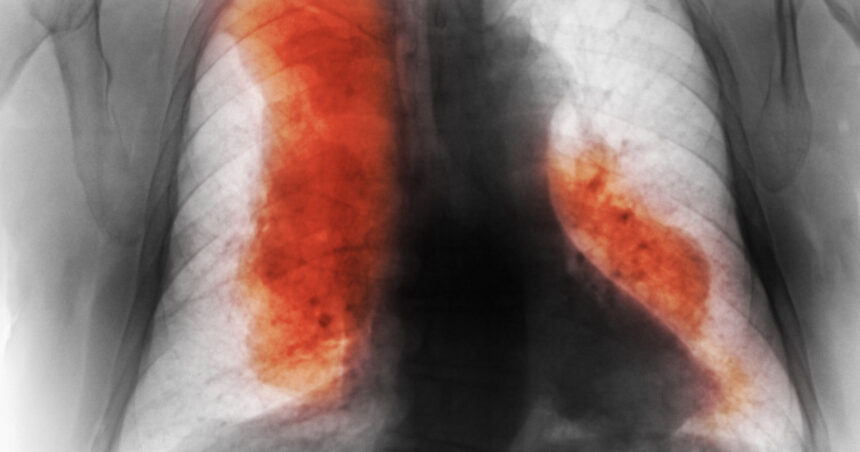

Majoritatea pacienților cu cancer provin din țări cu venituri mici și medii. Cancerul mamar a fost cel mai frecvent diagnosticat tip de cancer în 2023, în timp ce cancerele traheale, bronhice și pulmonare sunt cele mai frecvente cauze de deces.